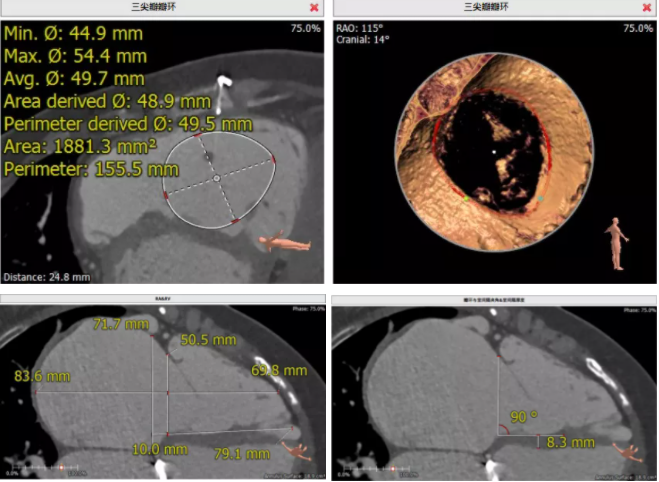

患者為68歲女性,14年前因“反復(fù)感冒、氣促”,檢查發(fā)現(xiàn)心臟瓣膜病,接受了“二尖瓣機(jī)械瓣置換術(shù)”。約5年前出現(xiàn)雙下肢水腫,活動(dòng)后心累氣緊,心臟彩超提示:三尖瓣返流。近年來(lái)三尖瓣返流逐漸加重并伴有輕微黃疸、雙下肢水腫,雖長(zhǎng)期服用利尿劑治療,但效果欠佳。郭惠明教授團(tuán)隊(duì)結(jié)合病史、超聲及CT評(píng)估,考慮患者瓣膜置換術(shù)后,三尖瓣重度返流,再次開(kāi)胸行體外循環(huán)手術(shù)風(fēng)險(xiǎn)高,經(jīng)團(tuán)隊(duì)整體評(píng)估,決定采用最適合患者的LuX-Valve三尖瓣置換系統(tǒng)行微創(chuàng)治療,根據(jù)測(cè)量結(jié)果選擇植入JS/TTVI-28-55型號(hào)的LuX-Valve瓣膜。